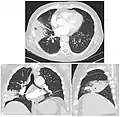

CT scan of the same case.

The identification of the infectious organism (or other cause) is an important part of modern treatment of pneumonia. The anatomical patterns of distribution can be associated with certain organisms,[6] and can help in selection of an antibiotic while waiting for the pathogen to be cultured.